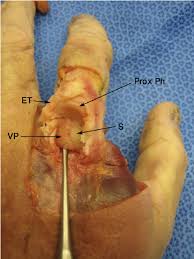

Central slip and mallet finger management effectively manage extensor tendon injuries of the finger to prevent disfigurement and. Learn how this injury is managed by reading here. Finger sprains and dislocations are injuries to the ligaments and soft tissues around the finger's small joints. Chat 1:1 with a doctorlicensed experts are available 24/7. Swelling, deformity, and pain are signs and symptoms that characterize a dislocated finger. When a finger gets dislocated, the bones become out of alignment with the joint and are no longer together. I'd go back to the doctors if it is causing any discomfort. Check if the user seeks of the index are increasing with every select on the table u r using unless the server is restarted this will give you a clear idea which index is being used or not. Sometimes, these ligaments do not heal adequately and surgery is occasionally needed to. It occurs when the bones of the finger are moved (dislocated) from their normal position. Every finger has three joints except the. Here you may to know how to tell if finger is dislocated. This condition may occur after a traumatic injury to the.